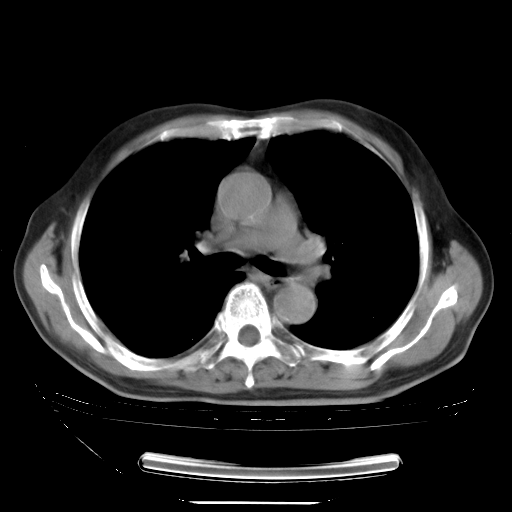

胸腹部CT,诊断意见:左上肺叶钙化灶、左侧胸膜局限性增厚并钙化、胆囊炎。描述部分肺组织呈磨玻璃样改变。

今天复查肺部CT,发现双肺广泛磨玻璃样改变。所以我把3月19日和5月9日相隔50天的肺部CT上传。请大家会诊。

2009年3月19日肺部CT片。

2009年3月19日肺部CT

大致读了系列胸部CT:纵隔窗无明显异常,肺窗:从4、27至今:主要是双肺中下野外带可见毛玻璃样改变,目前处于急性肺泡炎阶段,至于原因考虑1、结替组织或胶原血管性疾病所致?2、恶性疾病如恶组在肺部所致的表现或细支气管肺泡癌?3、药物或其它原因如肺蛋白沉着症所致肺泡炎目前不太可能?总之,明天就去请我院的呼吸科、感染科、血液科和临免专家会诊哈。